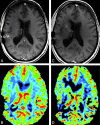

Fig 1.

A and C, Postcontrast SPGR image for reference MRI (C) shows new enhancement along the right anterior limb of the internal capsule, which was not present on comparison postcontrast SPGR (A). B and D, This area shows increased CBV on the concurrent DSC color map (D) compared with the prior DSC color map (B). The appearance was most suggestive of tumor progression, and the management plan was altered accordingly. Susceptibility artifacts are seen along the previous resection cavity in the right temporoparietal region on all images.